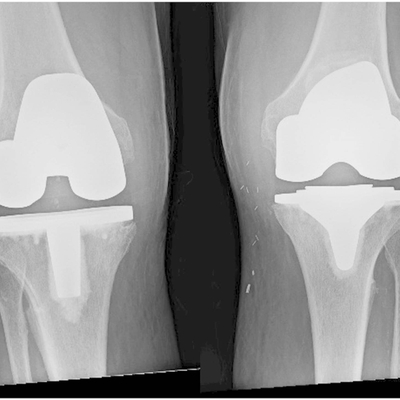

Click on an image below to view more info.